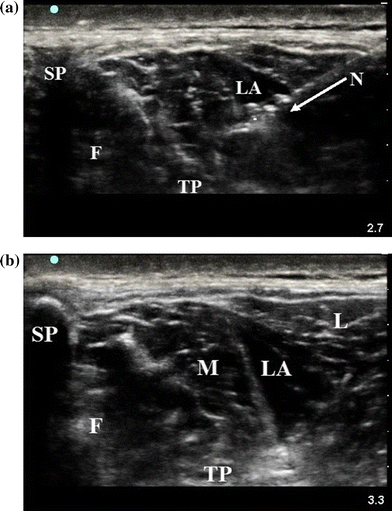

Lidocaine 1% was used to anesthetize the skin and subcutaneous tissues. A 10-cm 21G Stimuplex® needle (Braun Medical Inc, Bethlehem, PA, USA) was inserted bevel up in a lateral-to-medial orientation at an approximate angle of 30° to the skin. The needle was advanced under real-time in-plane ultrasound guidance through the belly of the LG towards the MF. The needle tip was directed towards the LG-MF interface deep to the midpoint (Fig. 3a). After an attempted aspiration with a 3-mL syringe was negative for blood, a 20-mL syringe was used to inject a small volume of local anesthetic to confirm needle tip placement between the MF and LG (i.e., hydrodissection). The location within the desired plane was facilitated by advancing the needle into the MF and subsequently injecting the local anesthetic as the needle was withdrawn. Ropivacaine 0.2% (without epinephrine) was incrementally injected with intermittently repeated negative aspiration. Anterior spread of local anesthetic was viewed as favourable (Fig. 3b). The block was administered bilaterally to each volunteer by injecting ropivacaine 40 mL in total (i.e., 20 mL injected into each side). The site of injection was subsequently marked with a felt-tip pen. The volunteers were monitored for signs or symptoms of local anesthetic systemic toxicity or other complications, with no report of any adverse reactions.

a Ultrasound image with needle placement. This image was obtained after injection of local anesthetic (approximately 2 mL) to confirm placement. Needle orientation is lateral to medial. SP = spinous process; F = facet joint; LA = local anesthetic; N = needle (arrow immediately below needle showing trajectory); TP = transverse process. b Ultrasound image after injection of local anesthetic (20 mL) and after needle removal. This image is at the level of injection, showing hydrodissection. SP = spinous process; F = facet joint; TP = transverse process; M = multifidus muscle; LA = local anesthetic; L = longissimus muscle